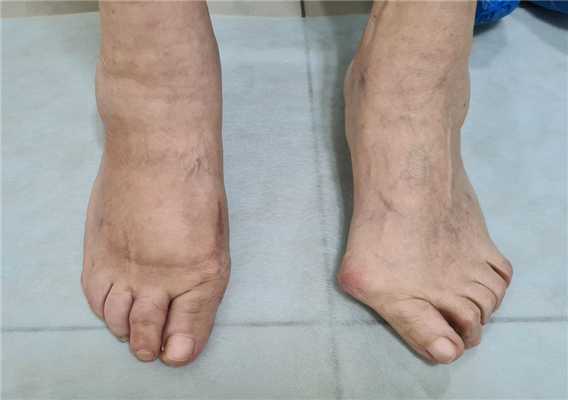

Косточка на большом пальце ноги, тяжёлый случай

Часто пациенты обращаются на запущенных стадиях заболевания, когда происходит не только смещение большого пальца кнаружи с образованием «косточки» в области головки первой плюсневой кости, но также появляется молоткообразная деформация 2-3-4 пальцев, внутреннее отклонение 5 пальца, появление косточки в области головки 5 плюсневой кости, возникновение болей под головками 2-3 плюсневой кости.

Все эти деформации требуют дополнительных вмешательств и значительного расширения объёма операций.

Клинический пример, пациентке 75 лет, деформация у неё начала прогрессировать с 20 летнего возраста. Что же произошло за это время?

- Первая плюсневая кость отклонялась всё дальше кнутри, а первый палец соответственно отклонялся кнаружи

- Сесамовидный гамачок вывихнулся и оказался между 1 и 2 плюсневыми костями

- Нагрузка постепенно полностью ушла с первого пальца и перешла на головку второй плюсневой кости

- Произошло разрушение капсулы 2 плюсне-фалангового сустава, второй палец вывихнулся кверху

- Нагрузка частично перешла на 3-4 плюсневые кости, и это вызвало их перегрузку и формирование молоткообразной деформации 3-4 пальцев

Внешний вид стопы после операции.

Через 12 недель отёк в большей степени регрессировал. Наружное искривление 1 пальца недокорректировано, молоткообразная деформация 2-го пальца устранена. Поперечный свод восстановлен

Нормальная парабола головок плюсневых костей восстановлена в обеих плоскостях. Определяется консолидация 2-3-4 плюсневых костей несмотря на отсутствие фиксации. Первая плюсневая кость находится в не оптимальной позиции.